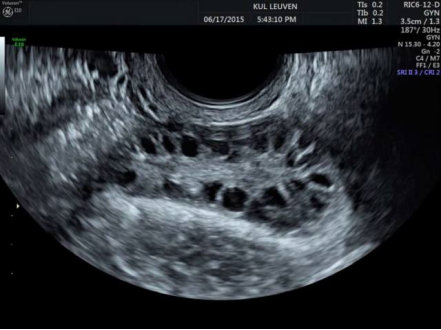

B超:监测卵泡生长和优势卵泡破裂可以作为排卵的证据,最为准确。

子宫及附件的超声检查,主要检查子宫大小、内膜厚度、形态、卵巢大小、卵泡个数等,及时发现子宫异常、输卵管积液、卵巢囊肿等异常。